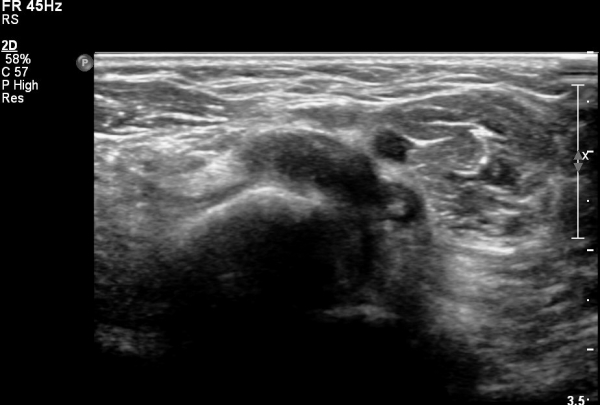

ÆÈ²ÞÄ¡ ¾Õ ÀÌµÎ¹Ú±Ù°Ç È¸´Ü¸ç°Ë»ç¿¡¼­ ÀÌµÎ¹Ú±Ù°Ç ¿ÜÃø¿¡ ¼ö¾×Àú·ù°¡ °üÂûµÊ(»çÁø 1).

ŽÃËÀÚ¸¦ ¸»´ÜºÎ·Î À̵¿ÇÏ´Ï ¿ä°ñµ¶±â ÀÌµÎ¹Ú±Ù°Ç ÂøºÎ¿¡¼­ °ÏÀÌ Àú¿¡ÄÚ ºÎÁ¾ »óÅ·Π°üÂûµÇ°í(»çÁø 2)